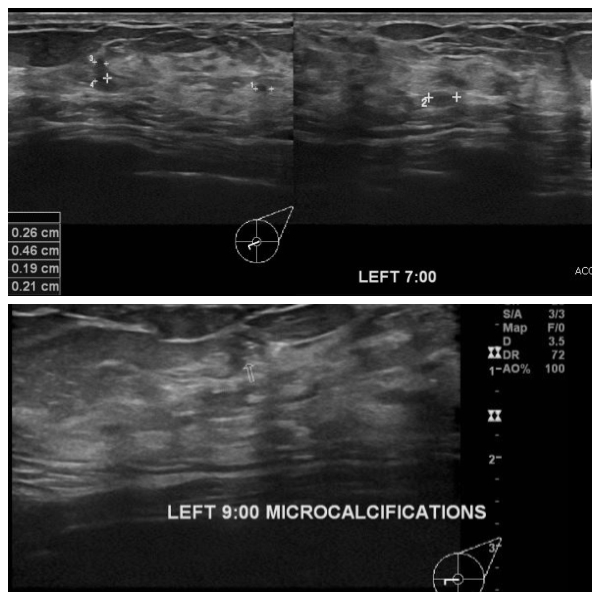

좌측 유방 통증과 유두 분비물로 내원한 50대 여성 분으로 본원 초음파 시행 후

좌측 7시, 9시  방향 유두 밑 중심핵생검 시행하여 좌측 유관암 진단 되었습니다.